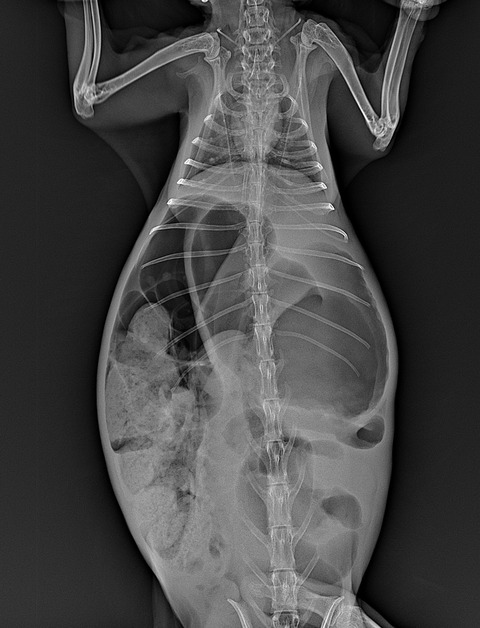

⇩異常な量の消化管ガス貯留が見られた症例

(⇩急性胃拡張)